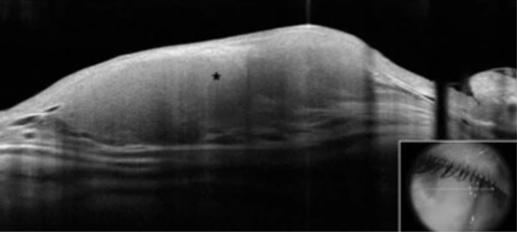

Figure 3. Anterior segment optical coherence tomography scan showing homogeneous, hyporeflective lesion with thin overlying epithelium.[2] Open access under terms of the Creative Commons License: http://creativecommons.org/licenses/by/4.0/. Original figures available at: https://eandv.biomedcentral.com/articles/10.1186/s40662-019-0151-4.